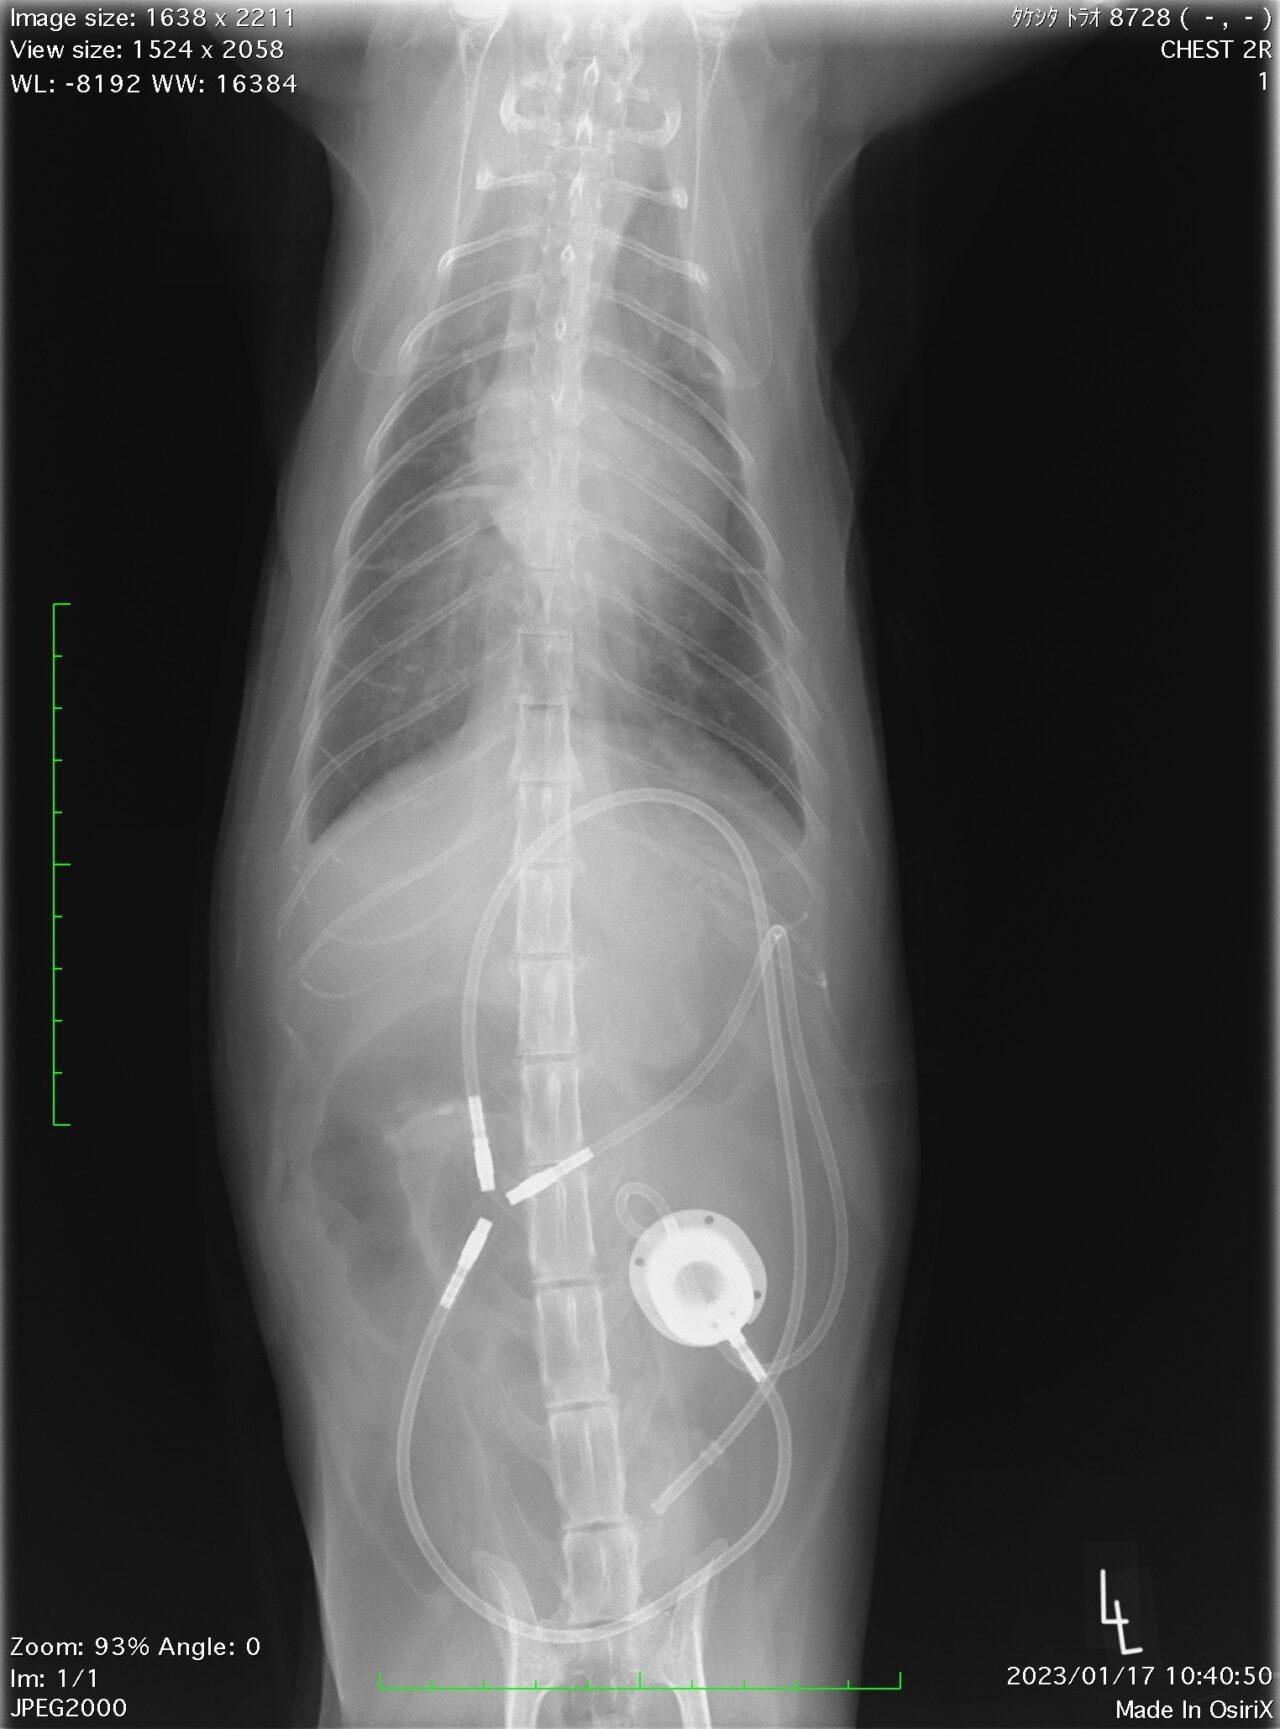

術後の写真ではこのようになります。

管がいっぱいありますが、この管が尿管の代わりとなり尿路を確保してくれます。